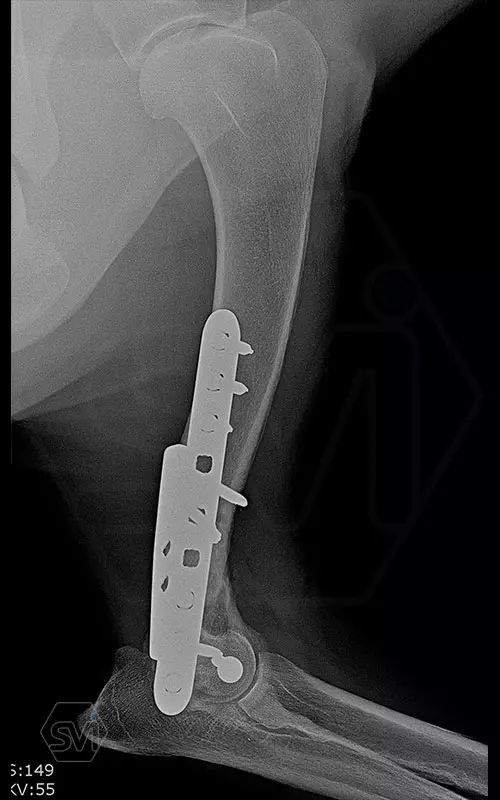

The damaged area was exposed laterally and medially, and 2 locking plate were used: a large polyiaxial straight plate made with 3.5 mm screws, and a small polyaxial plate laterally with 2.7 mm screws.

The intercondylar fragments were fixed with 3.5mm lag screw with a washer under the head.